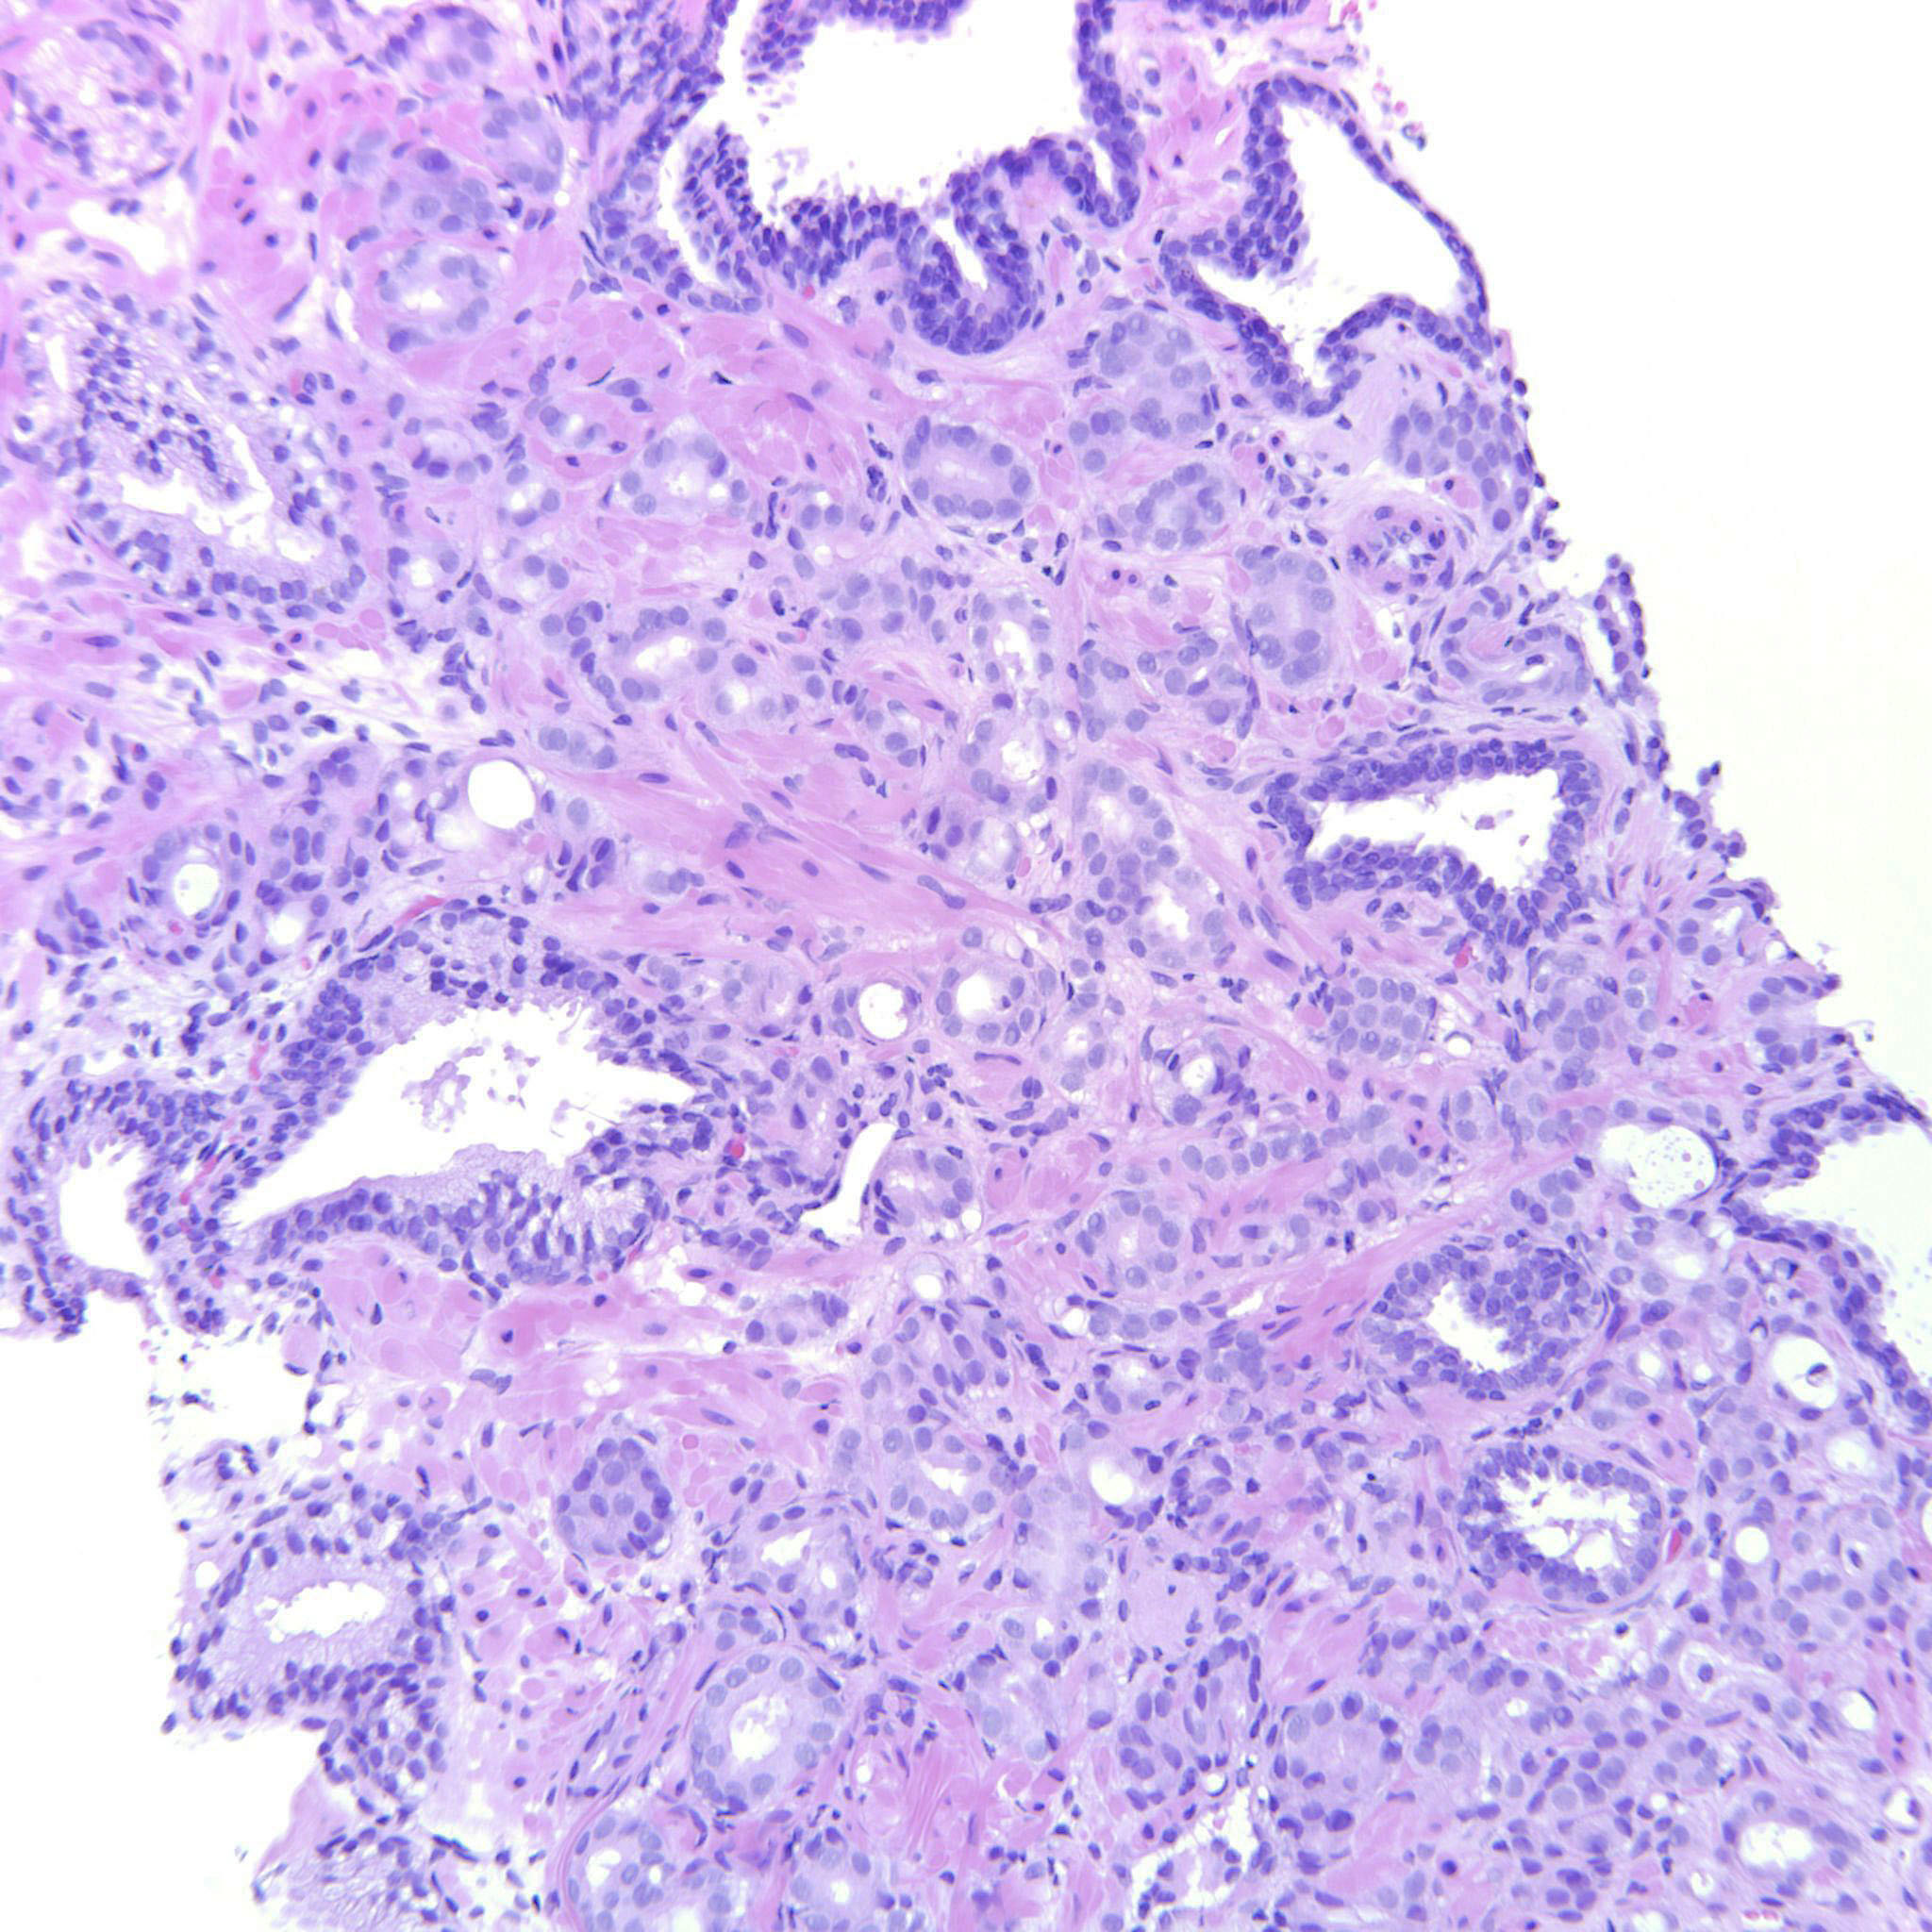

Prostate cancer grading

Case ID: 487